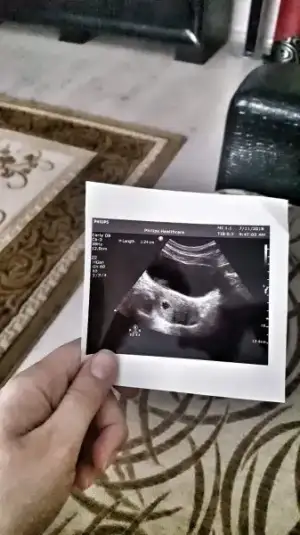

Kizlarr güzel haberlerle geldim çok şükür 5+3 olmamız gerekiyordu sata göre ama doktor 5+5 dedi neye göre belirleniyor embryo 2.6 mm buna göre mi ? Kalp atışı alıyor gibiyim minik bir hareket var ama haftaya tekrar gel dedi :) bir de erkek galiba dedi çok şaşırdım ya :)

Benim de seninle aynıymis bak kese olcusu bana bide kanama alanı var git dusur de kurtajdan kurtul dedi yüzüme karşı 1.27cm yani 12.7mm yapiyo yani senden 2 milim daha fazla ve bos kese ama çok şükür bugün kalbini duydum panikleme uzulme

Canimmm sakin ağlama bak ben bir haftadır ağlıyorum hem leke geliyordu hemde kese var bebek yoktu boş gEbesin dedi biri o kadar üzüldüm ki ama bu hafta bebeğimi ve kalp atisini aldım az önce bak sana g3cen haftaki kesem

Canm bende suan ayni resim hemen hemen boş diye çok evham yaptim ins bende görür ve duyarım canm Eki Görüntüle 2170579 Eki Görüntüle 2170579